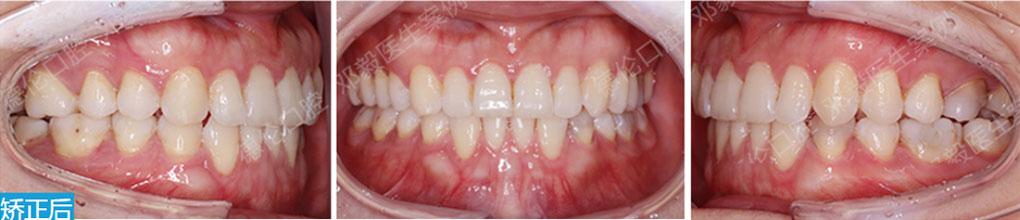

德倫口腔矯正診室指定專家團是以德倫口腔總院正畸科主任、時代天使全國智美隱形矯治病例大賽三等獎得主――熊小琴主任,和德倫口腔總院正畸科資深專家、隱形矯正培訓講師、有 26 年口腔醫療臨床經驗的王蘇靜醫生,共同領銜的 16 位隱形正畸認證醫師。指定專家團實力雄厚,臨床經驗豐富,內含多名口腔正畸專業博士、碩士組成的正畸博碩專家團和第 18 屆雅加達亞運會中國代表團時代天使口腔保障營專家團。